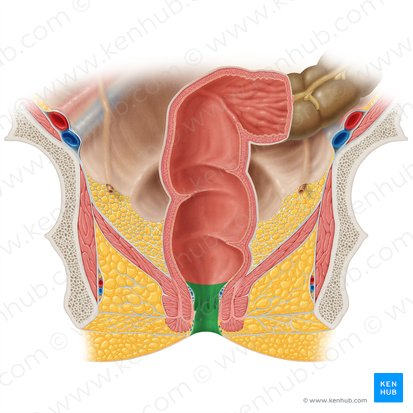

Rectum

the final section of the large intestine, terminating at the anus, that stores feces before elimination.

Anus

the opening at the end of the digestive tract through which feces are eliminated from the body.

Internal Anal Sphincter

A thickened ring of smooth muscle that surrounds the anal canal. It is under involuntary control, meaning you don't consciously control its contraction or relaxation. It is normally contracted to maintain fecal continence.

Rectum

The final section of the large intestine, terminating at the anal canal. Its primary function is to store feces before they are eliminated from the body.

External Anal Sphincter

A ring of skeletal muscle that surrounds the anal canal, superficial to the internal anal sphincter. It is under voluntary control, meaning you can consciously choose to contract or relax it to control the passage of feces. This allows for the postponement of defecation.

Anus

The opening at the end of the digestive tract through which feces are eliminated from the body. It is surrounded by the internal and external anal sphincters, which regulate the passage of waste.